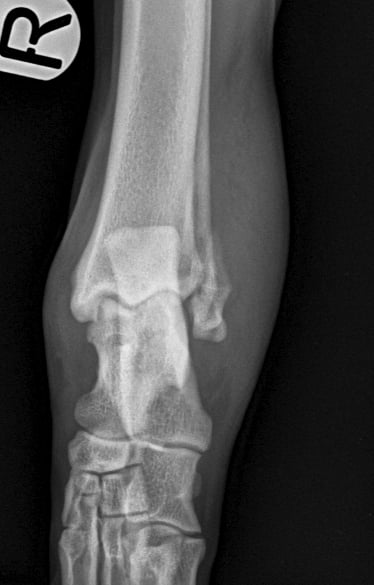

Lateral approach to the talocrural joint reveals severe oedema and bruising, 1.2mm IM pin placed in a distal to proximal fashion, 0.75mm cerclage wire used to create a figure-of-8 tension band. 1.4mm pin placed parallel to the talocrural joint from lateral to medial (Fig 3 and 4).

Fig. 3

Fig. 4